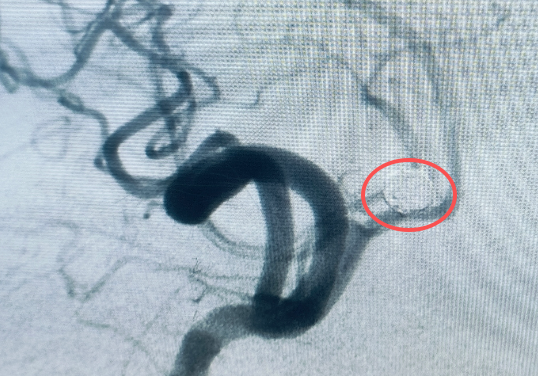

由于病情危急,当地医院初步检查后建议转至上级医院进一步治疗。随后,小张被 120 急救车转运至昆明三博脑科医院。医院紧急开通绿色通道,神经外科医护团队第一时间介入,结合头颅影像学检查结果,小张被确诊为 「颅内动脉瘤破裂出血」。

颅内动脉瘤被称为大脑里的 「不定时炸弹」,一旦破裂出血,血液会压迫脑组织,若不及时干预,不仅可能造成严重的语言障碍、肢体偏瘫,甚至会危及生命。情况刻不容缓,神经外科专家团队迅速制定手术方案,为小张紧急实施了 「脑动脉瘤介入栓塞术」。经过医护人员的全力救治,小张的出血情况得到控制,术后恢复良好,目前已脱离险境,即将康复出院。